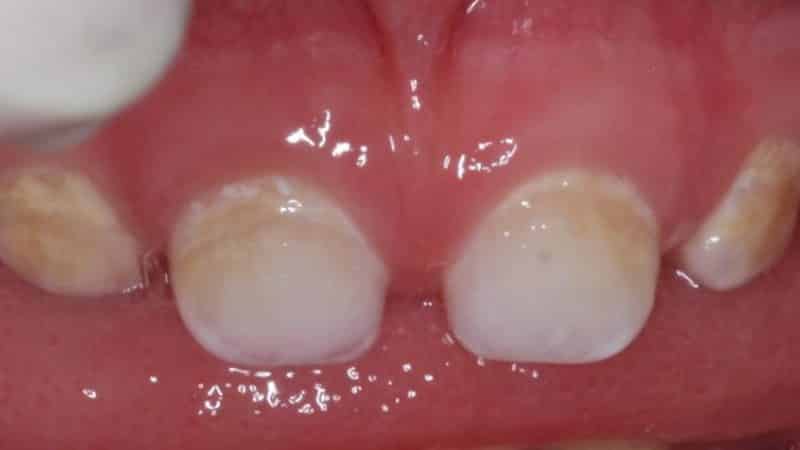

Снаружи заболевание проявляется в виде множества пятен, деформаций и углублений на зубной поверхности. Параметры поражений, такие как размер, форма и глубина, могут варьироваться. В некоторых случаях стоматологи фиксируют недоразвитие эмали в полостях или на жевательных выступах.

Цветовые оттенки пятен обычно находятся в светлом диапазоне: от белых и прозрачных до желтоватых. Края поражений имеют четкие контуры, а размеры симметричны аналогичным зубам на противоположной стороне. Поверхность дефектов может быть гладкой, с глянцевым или матовым финишем, в зависимости от степени нарушения минерализации.